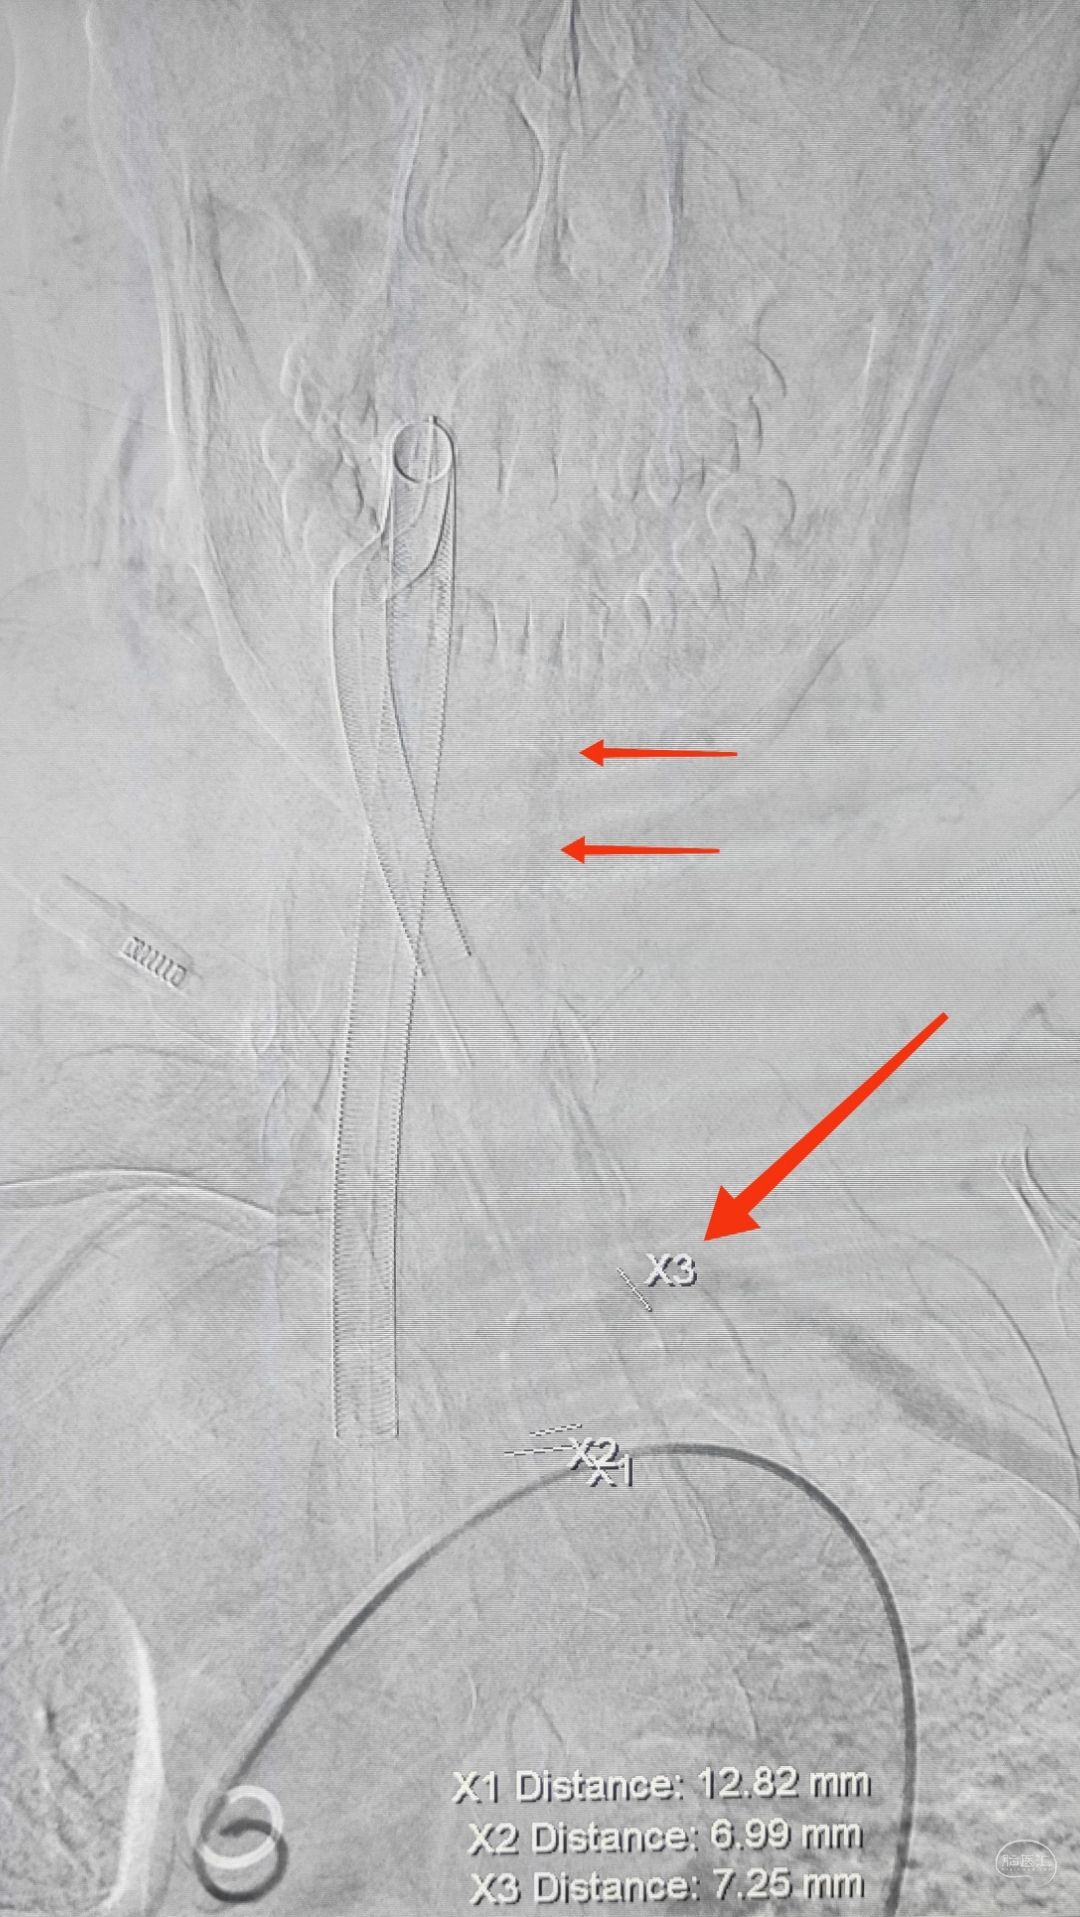

右侧锁骨下造影:右侧椎动脉开口也是重度狭窄,血流速度缓慢,闸门效应明显,此刻,不禁感叹血管的伟大,自己都狭窄得不要不要的了,还努力给对侧代偿供血,奉献精神佳!

1,0.035'泥鳅导丝引导,6F导引导管至右侧锁骨下动脉

2,泥鳅导丝不撤,留置与右侧肱动脉,维持导引导管稳定性

3,Synchro导丝过狭窄,微导管超选造影确认真腔(小心翼翼,略显谨慎),毕竟这个血管是个宝贝疙瘩

因为是极重度狭窄,支架前拟小球囊预扩,谨慎起见,置入泰杰Proender保护伞并打开,以免不测

梯度预扩,先雅培1.5×15小球囊预扩

再Sino3×20球囊预扩

预扩满意,保护伞不浪费,借助保护伞的支撑和保护作用,上送导引导管(不怕掉斑块,物尽其用),为颅内狭窄处理提供更佳支撑

看图说话,没啥聊的。球囊不浪费,Sino3×20球囊预扩V4狭窄

EP4.5×22支架置入

导引导管保持原位,导管内安全输送Herculink5×20,通过椎开口狭窄并走远,再回撤导引导管至锁骨下动脉

球扩支架顺利释放